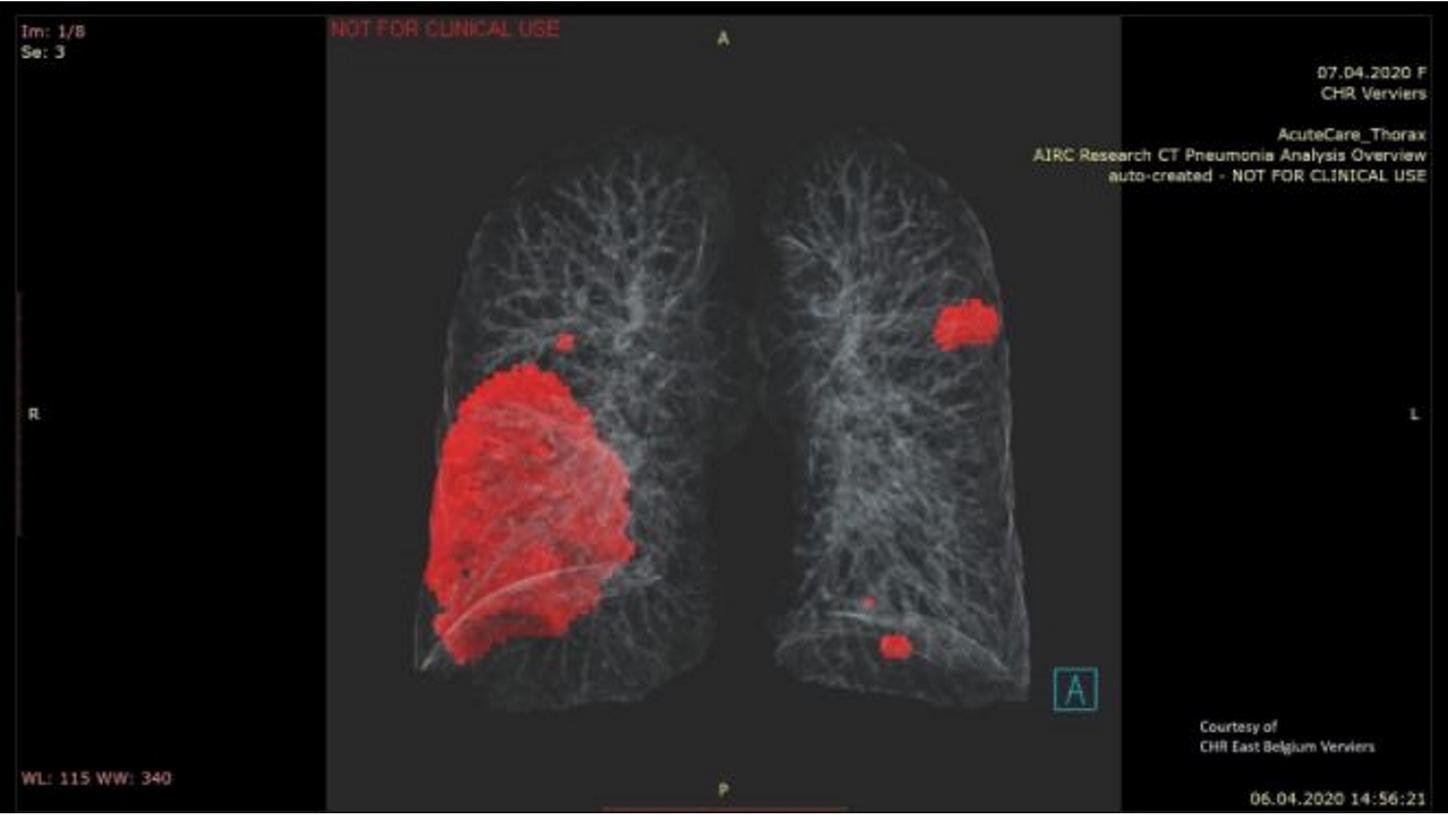

2 The AI-Rad Companion Chest CT Pulmonary Density feature falls under the FDA Enforcement Policy for Imaging Systems during the Coronavirus Disease 2019 (COVID-19) Public Health Emergency Section IV.C and is therefore not 510(k) cleared. It is not intended to be used to diagnose COVID-19. AI-Rad Companion Chest CT is not commercially available in all countries. Its future availability cannot be guaranteed.

- The development of the prototype algorithm and its deployment was a Siemens Healthineers collaborative effort, bringing together frontline healthcare providers, scientists and engineers from Princeton, clinical experts and developers from India, product development teams from CT, Digital Health and Syngo from Germany. The Pulmonary Density feature is new in VA12A without FDA Clearance. According to FDA policy “Enforcement Policy for Imaging Systems During the Coronavirus Disease 2019 (COVID-19) Public Health Emergency issued in April 2020, the manufacturer is allowed to market this feature without FDA-clearance. This policy is intended to remain in effect only for the duration of the public health emergency related to COVID-19 declared by the HHS Secretary in accordance with section 319(a)(2) of the Public Health Services Act (42 U.S.C. 247d(a)(2)). Pulmonary Density results are not indicated for the diagnosis of COVID-19. Only in vitro diagnostic testing is currently the definitive method to diagnose COVID-19.